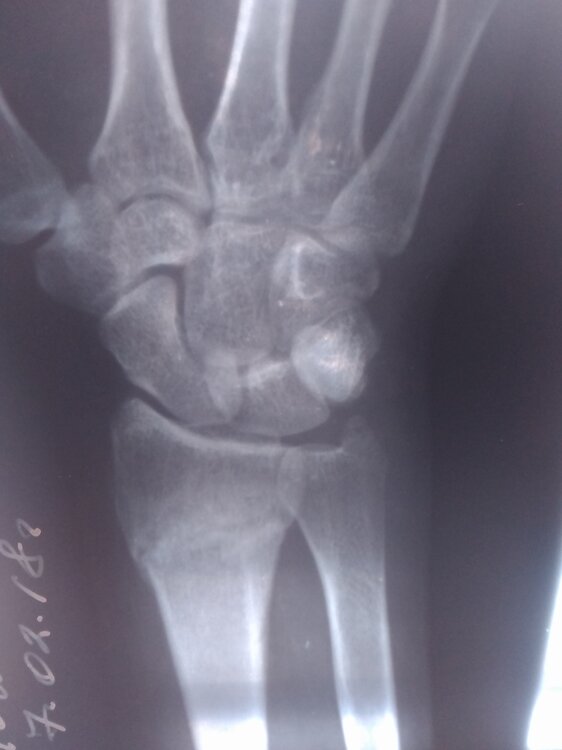

Sumchanka Опубліковано: 4 березня 2018 Автор Поділитись Опубліковано: 4 березня 2018 Хочу рассказать историю, которая сейчас происходит у нас с дочкой. Возможно кто-то для себя вынесет какой-то урок. Итак... Перед Новым годом дочка сломала левую руку в лучевой части перед кистью. Перелом был закрытый со смещением. Упала практически дома-перед калиткой соседей. И потом, толи от болевого шока, толи ещё по какой причине, нам не сказала, а поехала с друзьями в больницу. В трампункте городской больницы вправили, наложили гипс,вернее пародию на гипс-и не гипс и не лангета,ерунда короче... Врача закрепили ещё того ,"умника"- то справку не выпишу, то с кабинета нас выгонял, направление на контрольный снимок не давал-сплошные нервы. И вот, снимают гипс, а рука болит и болит, да плюс с подвижностью что-то не то. Обратились к зав. отделению, сделали снимок-результат: Перелом,который сростается(фото). И это спустя 35 дней... За это время он должен был сростись. И вот этот заведующий нам предлагает походить на процедуры и это при том, что снимок показал отклонение в сростании частей лучевой кости- как потом нам сказали в областной ортопедии-от 15 до 18°. Предложений от врачей городскоц ортопедии исправлять ситуацию не последовало, хотя спрашивала... Тогда подключили знакомых и договорились с одним из лучших ортопедов областной больницы ломать повторно руку, исправлять ось лучевой кости. Оставался вопрос :либо пластина, либо спицы. По ходу подготовки операции и в ходе её решили ставить спицы. И вот опять в гипсе ещё минимум на 1 мес + появился шов... А перед этим дочка делала снимки для заграничного модельного агенства. А теперь контракт под большим вопросом-есть требования по коже и её повреждениям... А ещё вся эта история случилась в разгар сессии-пытаемся хоть как-то закрыть. Да и начался новый семестр-тоже сдавать хватает чего. Несмотря на то ,что рука левая, чертежи и рисунки будущему архитектору делать очень затруднительно. Мораль: - дорогие родители-берите все в свои руки, а дети,даже взрослые-слушайтесь родителей; - без денег тебя зовут никак и ты для всех никто( по ходу лечения в городской больнице дали понять-если бы дочка поступила с родителями и с деньгами, то и гипс был бы другой и отношение...) Берегите себя и своих близких. Своевременная и правильная помощь позволит сьекономить и деньги и нервы . Всем здоровья! 17 Посилання на коментар Поділитися на інших сайтах More sharing options...